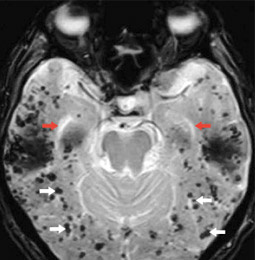

mri_alzheimer_gefaesserkrankung

Abb. 1b

Demenz bei Gefässerkrankung; die Hirnkammern sind schlank, aber zahlreiche Einblutungen in das Hirngewebe sind abgrenzbar (schwarze Punkte, gekennzeichnet mit weissen Pfeilen).